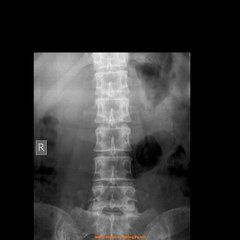

病例:女性,50歲,腰痛數年。(圖)

腰1-4椎體緣不同程度骨質增生,腰1-3椎體下緣許氏結節(腰3考慮合併軟骨結節,連同椎體後緣骨片向椎管內突出,導致局部

許莫氏結節椎管變窄)。系由於椎間盤變性,椎體的軟骨板破裂,髓核脫出突出入椎體內,造成椎體內出現半圓形缺損陰影,椎體中叫許莫氏結節,後緣叫軟骨結節,大多為單發,偶爾多發。好發於L4,次為L5和L2,可與椎緣骨並存,吳恩惠的<影象診斷學>認為椎緣骨也是髓核向前脫出形成的,如果不合併向椎體後緣突出,臨床可無神經根受壓體徵,骨內的軟骨結節連同椎體後緣骨質可突入椎管,故常合併椎間盤後突。發病機制:先天性解剖缺陷為因,慢性外傷起催化作用,骨內軟骨結節是果。骨內的軟骨結節連同椎體後緣骨質可突入椎管,常合併椎間盤後突。